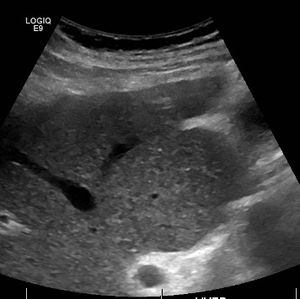

또한, 간기능 검사, 프로트롬빈 시간 측정, 식도위내시경 검사, 소변 검사, 복부 초음파, CT, MRI, Fibroscan 등을 통해 간의 상태를 확인한다.[181]

복부 초음파 검사나 복부 CT 검사에서는 종대된 간 좌엽과 위축된 간 우엽, '''메쉬 패턴'''(소망목상)의 실질, 둔화된 변연, 간 표면의 요철 등이 나타날 수 있다. 특히, "알코올성 간경변"에서는 재생 결절이 작고 균일하게 분포하여 양엽이 종대되고 실질은 거칠지 않으며 표면 요철도 눈에 띄지 않는다.

복부 초음파 검사에서는 간 재생 결절, 문맥 고혈압을 반영한 담낭 벽 비후, 방제 정맥 및 좌위 정맥 확장·비장후 복막 단락 등 측부 혈행로 형성, 복수 등을 추가로 확인할 수 있다.

복부 초음파 검사나 복부 CT 검사에서 다음과 같은 소견이 나타난다.

- 종대된 간 좌엽과 위축된 간 우엽

- '''메쉬 패턴'''(소망목상)의 실질

- 둔화된 변연

- 간 표면의 요철

- (알코올성 간경변의 경우) 재생 결절이 작고 균일하게 분포, 양엽 종대, 거칠지 않은 실질, 눈에 띄지 않는 표면 요철

복부 초음파 검사에서 다음과 같은 소견을 확인한다.

- 간 재생 결절

- 문맥압 항진을 반영한 담낭 벽 비후

- 방제 정맥, 좌위 정맥 확장·비장후 복막 단락 등 측부 혈행로 형성

- 복수